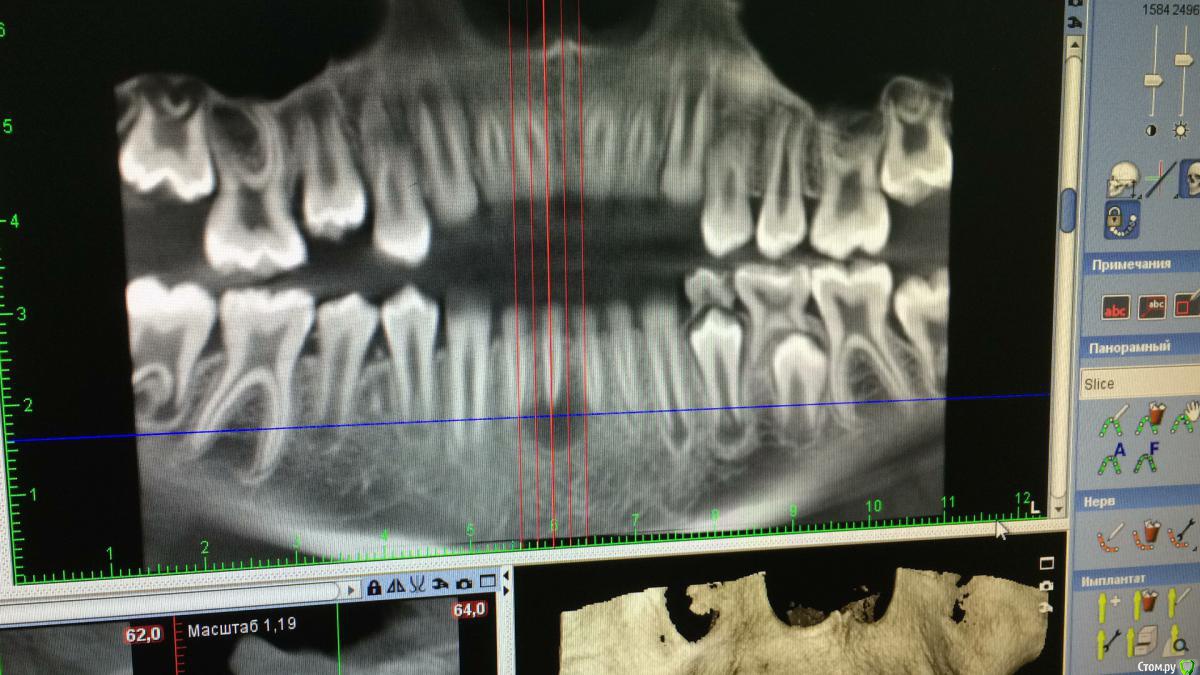

DenisV Опубликовано 15 февраля, 2017 Поделиться Опубликовано 15 февраля, 2017 Коллеги кто что думает? Мальчик 12 лет обратился с жалобами на боль в зубе 4.1, зуб раскрыт, получен эксудат из канала. Ссылка на комментарий

DenisV Опубликовано 16 февраля, 2017 Автор Поделиться Опубликовано 16 февраля, 2017 Коллеги кто что думает? Мальчик 12 лет обратился с жалобами на боль в зубе 4.1, зуб раскрыт, получен эксудат из канала.Зуб был ранее интактен в госке зуб открыли и назаначили полоскания, сейчас подвижность 2-3 степени. Мама отмечает ранее травму этого зуба. Ссылка на комментарий

Давлетшин Опубликовано 20 февраля, 2017 Поделиться Опубликовано 20 февраля, 2017 (изменено) Добавлю, что кажется, что канал раздваивается на середине корня, по фото плохо видно. Т.е. кальций в оба канала. и каналы очень хорошо мыть и УЗ. а по размеру разряжения не особо страшно.И что между 44 и 45? Изменено 20 февраля, 2017 пользователем Давлетшин Ссылка на комментарий